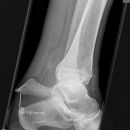

Calcaneus